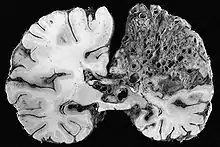

In the brain, AVMs occasionally exert pressure, leading to headaches. They may also increase the risk of seizures, as would any abnormal tissue in the brain. Finally, hemorrhage from an AVM may lead to intracerebral hemorrhage (bleeding into the brain), which causes any of the symptoms of stroke such as weakness in part of the body or difficulty speaking. If the bleeding occurs into the subarachnoid space (subarachnoid hemorrhage), there is usually a severe, sudden headache and decreased level of consciousness and often weakness in part of the body.[1][2]

Brain AVMs

The decision to treat brain arteriovenous malformations depends on the symptoms that they cause (such as seizures or headaches). The bleeding risk is predicted by previous episodes of hemorrhage, and whether on the CTA or MRA scan the AVM appears to be deep-seated or have deep venous drainage. Size of the AVM and the presence of aneurysms appears to matter less.[14] In HHT, some lesions (high-flow arteriovenous fistulae) tend to cause more problems, and treatment is warranted. Other AVMs may regress over time without intervention.[7] Various modalities are available, depending on the location of the AVM and its size: surgery, radiation-based treatment and embolization. Sometimes, multiple modalities are used on the same lesion.[2][14]

Surgery (by craniotomy, open brain surgery) may be offered based on the risks of treatment as determined by the Spetzler–Martin scale (grade I-V); this score is higher in larger lesions that are close to important brain structures and have deep venous drainage. High grade lesions (IV and V) have an unacceptably high risk and surgery is not typically offered in those cases. Radiosurgery (using targeted radiation therapy such as by a gamma knife) may be used if the lesion is small but close to vital structures. Finally, embolization may be used on small lesions that have only a single feeding vessel.[14]